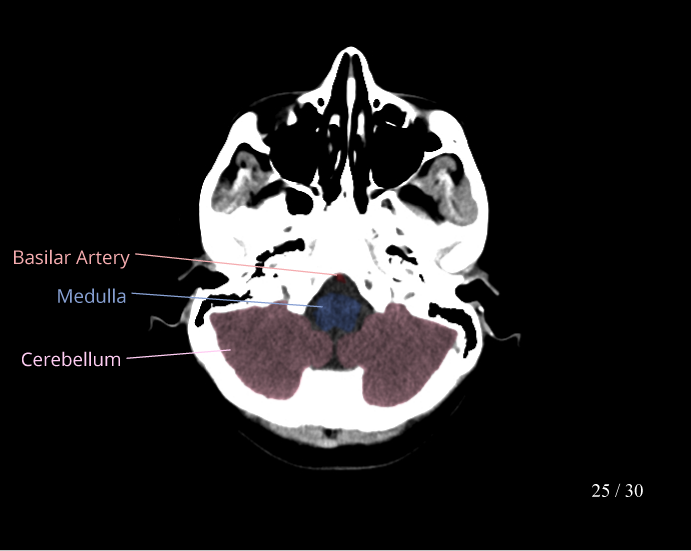

CT Brain Anatomy